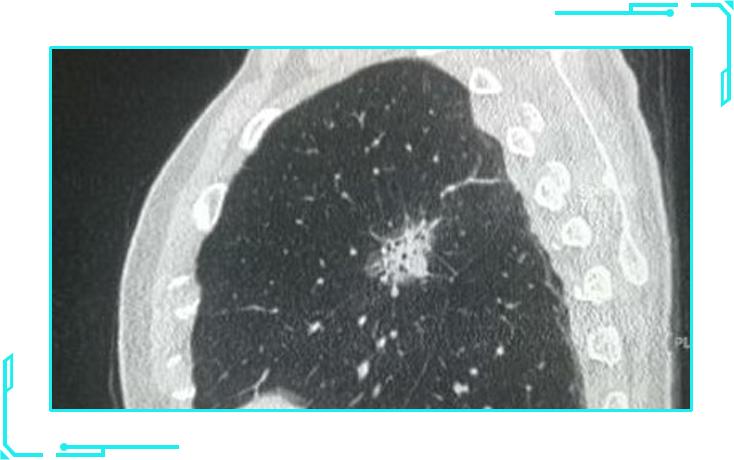

在薄层CT上,根据肺结节的密度大小,将肺结节分为以下三种:

1纯磨玻璃结节

纯磨玻璃结节,影像表现像磨砂玻璃一样,看起来影像比较虚。

2部分实性磨玻璃结节

部分实性磨玻璃结节就如同一个荷包蛋,磨玻璃成分类似其中的蛋清,而实性且密度较高的部分则类似蛋黄。

3纯实性结节

纯实性结节类似于单独分离的蛋黄,是一个实性且密度较高的病灶。